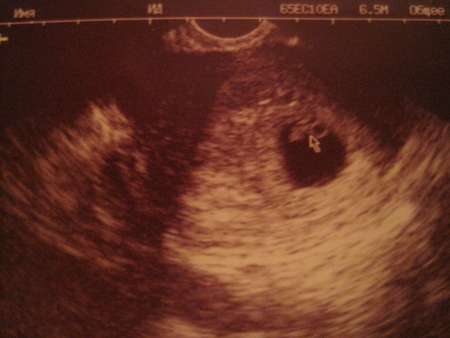

А я картинку увидела и уж собралаь вас опять поздравлять

!